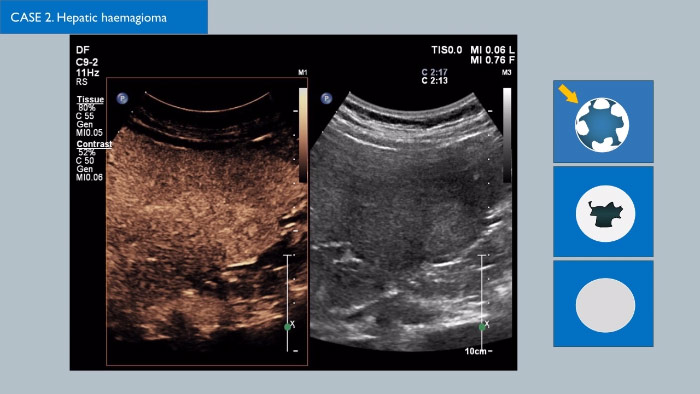

Ultraschall-Kontrastmittel können die Rolle des Ultraschalls verändern: Verstärkungsmuster von Leberläsionen können in Echtzeit untersucht werden, was zu einer schnelleren und fundierteren Diagnose führt.

Bei den Ultraschallsystemen von Philips ist der kontrastmittelverstärkte Ultraschall nahtlos in den Standard-Arbeitsablauf integriert und bietet so ein hohes Maß an Darstellungsdetail in der arteriellen, portalvenösen und Spätphase. Zusätzlich bieten moderne Technologien wie MaxVue, PureWave C9-2 Schallkopf, Fusionsbildgebung und die integrierte Quantifizierung über die Philips Q-Apps dem Anwender Sicherheit, sodass die Untersuchung der Leber ungeahnt einfach und intuitiv wird, ungeachtet der Komplexität der Untersuchung. Innovative Lösungen wie die xMATRIX 3D/4D-Technologie verändern die Beurteilung von Läsionen in der Leber ebenfalls und bieten eine schnelle und effektive Möglichkeit, Versorgungsgefäße sowie das Ansprechen auf eine Behandlung darzustellen. Es gibt viele spannende Entwicklungen im Bereich von CEUS; klicken Sie auf den Link, um Kontakt mit Ihrem zuständigen Philips Vertriebsteam aufzunehmen.